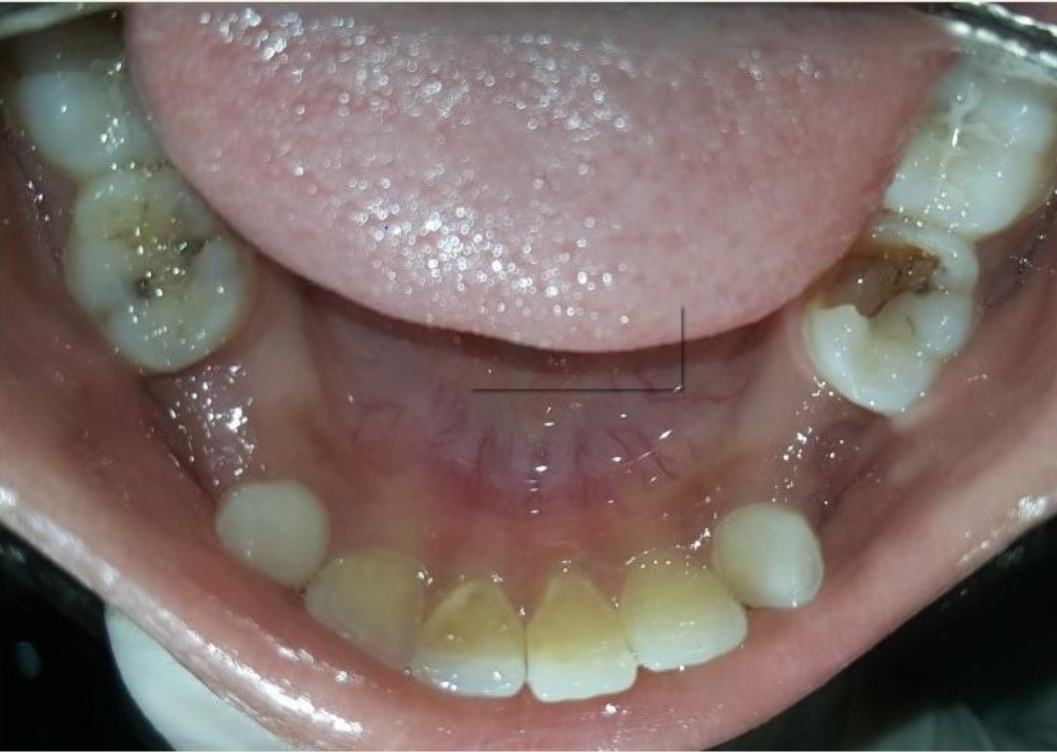

A nine year old boy reported to the Department of Pedodontics and Preventive Dentistry of Bharati Vidyapeeth Deemed University, Sangli with a chief complaint of pain and abscess in the lower left back region of the jaw since one month. Patient was a known case of autism spectrum disorder. He was inattentive, hyperactive and showed repetition of gestures. Psychological testing report showed childhood autism rating scale (CARS) 2, which falls into mild to moderate autistic category. Vineland social maturity scale (VSMS) measuring the social intelligence of child was found to be 31.5 with social age of around 5-6years. The family history was non-contributory. He was not on any medications and had reported no history of drug allergies. Extra-oral examination showed no specific findings (Figure 1). Intraoral examination revealed multiple carious lesions (Figure 2) (Figure 3). Occlusal caries involving enamel, dentin and pulp with 55 and 75. Intra oral dentoalveolar abscess was also seen in relation with 75 (Figure 4). Dentinal caries was seen with 85 and occlusal pit and fissure caries was seen with 65. No soft tissue abnormalities were appreciated. Radiographic evaluation by orthopantomogram was also done which revealed no abnormality (Figure 5). It was difficult for the patient to co-operate on the dental chair and understand the instructions given to him; hence treatment was planned under general anaesthesia. A complete pre anaesthetic evaluation was done and the patient was categorized under ASA II. Treatment plan was explained to the child’s parents and a written consent was obtained from them. The dental treatment done under general anaesthesia included pulpectomy of 55, 75 with glass ionomer cement restoration followed by placement of pre trimmed and pre contoured stainless steel crowns (Figure 6) (Figure 7). Glass ionomer cement restorations were done in 65 and 85 and pit and fissure sealants application on 16, 26, 36 and 46. Post-operative orthopantomogram showed well placed restorations and crowns (Figure 8). Patient’s post-operative recovery was uneventful. Treatment rendered reduced the pain and discomfort.Oral hygiene care instructions were given to the parents and maintenance protocol was explained and they were also encouraged for regular follow-up for preventive dental care. The two months follow-up revealed improved eating habits of the child.

Figure 3 Intra oral pre-operative image of the mandible.

Figure 7 Stainless steel crown cemented on 75 and glass ionomer cement restoration on 85 and Sealants on 36, 46.